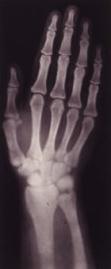

Nur wenige Entdeckungen haben die Medizin, aber auch die Technik und Wissenschaft, so beeinflusst, wie die Röntgenstrahlen. Wilhelm Conrad Röntgen hat sie bei seinen Forschungen mit Kathodenstrahlen am Abend des 8. November 1895 entdeckt, und sie aufgrund ihrer unbekannten physikalischen Eigenschaften Zeit seines Lebens "X-Strahlen" genannt. In seinem Vortrag vor der Physikalisch-Medizinischen Gesellschaft an der Universität Würzburg am 23. Januar 1896

hatte er den Anstoß zur medizinischen Auswertung gegeben, indem er neben Aufnahmen technischer Gegenstände als Demonstrationsobjekt auch seine Hand und die seiner Frau röntgenphotographisch darstellte. |